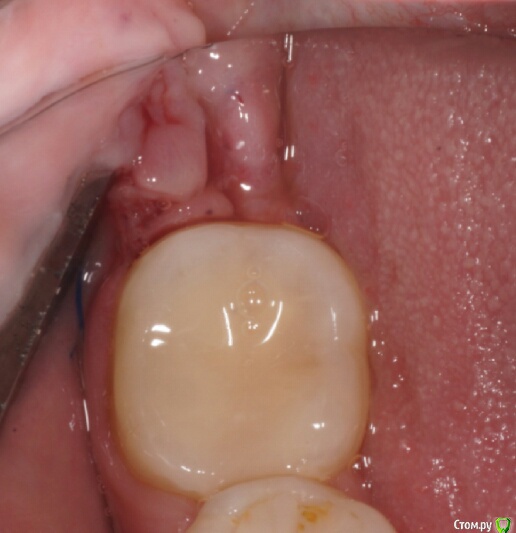

колесников Опубликовано 16 апреля, 2017 Автор Поделиться Опубликовано 16 апреля, 2017 Иногда кажется ,что лоскут выделить язычно не возможно и наглухо ушить не удасться,особенно в случаях когда 8ка полностью прорезалась. Это только так кажется. Ссылка на комментарий

Irouil Опубликовано 16 апреля, 2017 Поделиться Опубликовано 16 апреля, 2017 Графт был? Ссылка на комментарий

колесников Опубликовано 17 апреля, 2017 Автор Поделиться Опубликовано 17 апреля, 2017 К сожалению нет. Ссылка на комментарий

колесников Опубликовано 17 апреля, 2017 Автор Поделиться Опубликовано 17 апреля, 2017 (изменено) В данном случае развёрнутый. Опрокинутый когда 8ка не прорезалась,самый простой вариант. Да,в щели вижу всю проблему вторичного инфицирования,для прикрытия вероятного расхождения краев раны за 7кой,делаю второй лоскут. Изменено 17 апреля, 2017 пользователем колесников Ссылка на комментарий

колесников Опубликовано 6 мая, 2017 Автор Поделиться Опубликовано 6 мая, 2017 Воспользовался случаем попрактиковаться в выделении язычного лоскута. Разрез поверхностный,далее расщепление и выделение.По поводу лоскута без графта. Дважды пришлось так поступить. В первом случае расхождение краев за 7кой с образованием щели и застревание пищи. Во втором случае мезиально все герметично,дистально (?) щель,при зондировании -пусто. Итого: лоскут без графта-так себе вариант. Ссылка на комментарий